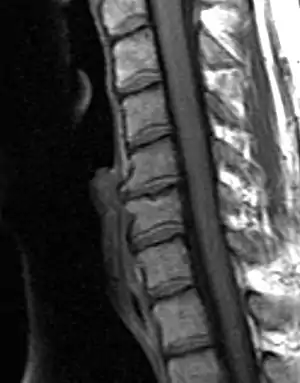

Degenerated disc between C5 and C6 (vertebra at the top of the picture is C2), with osteophytes anteriorly (to the left) on the lower portion of the C5 and upper portion of the C6 vertebral body.